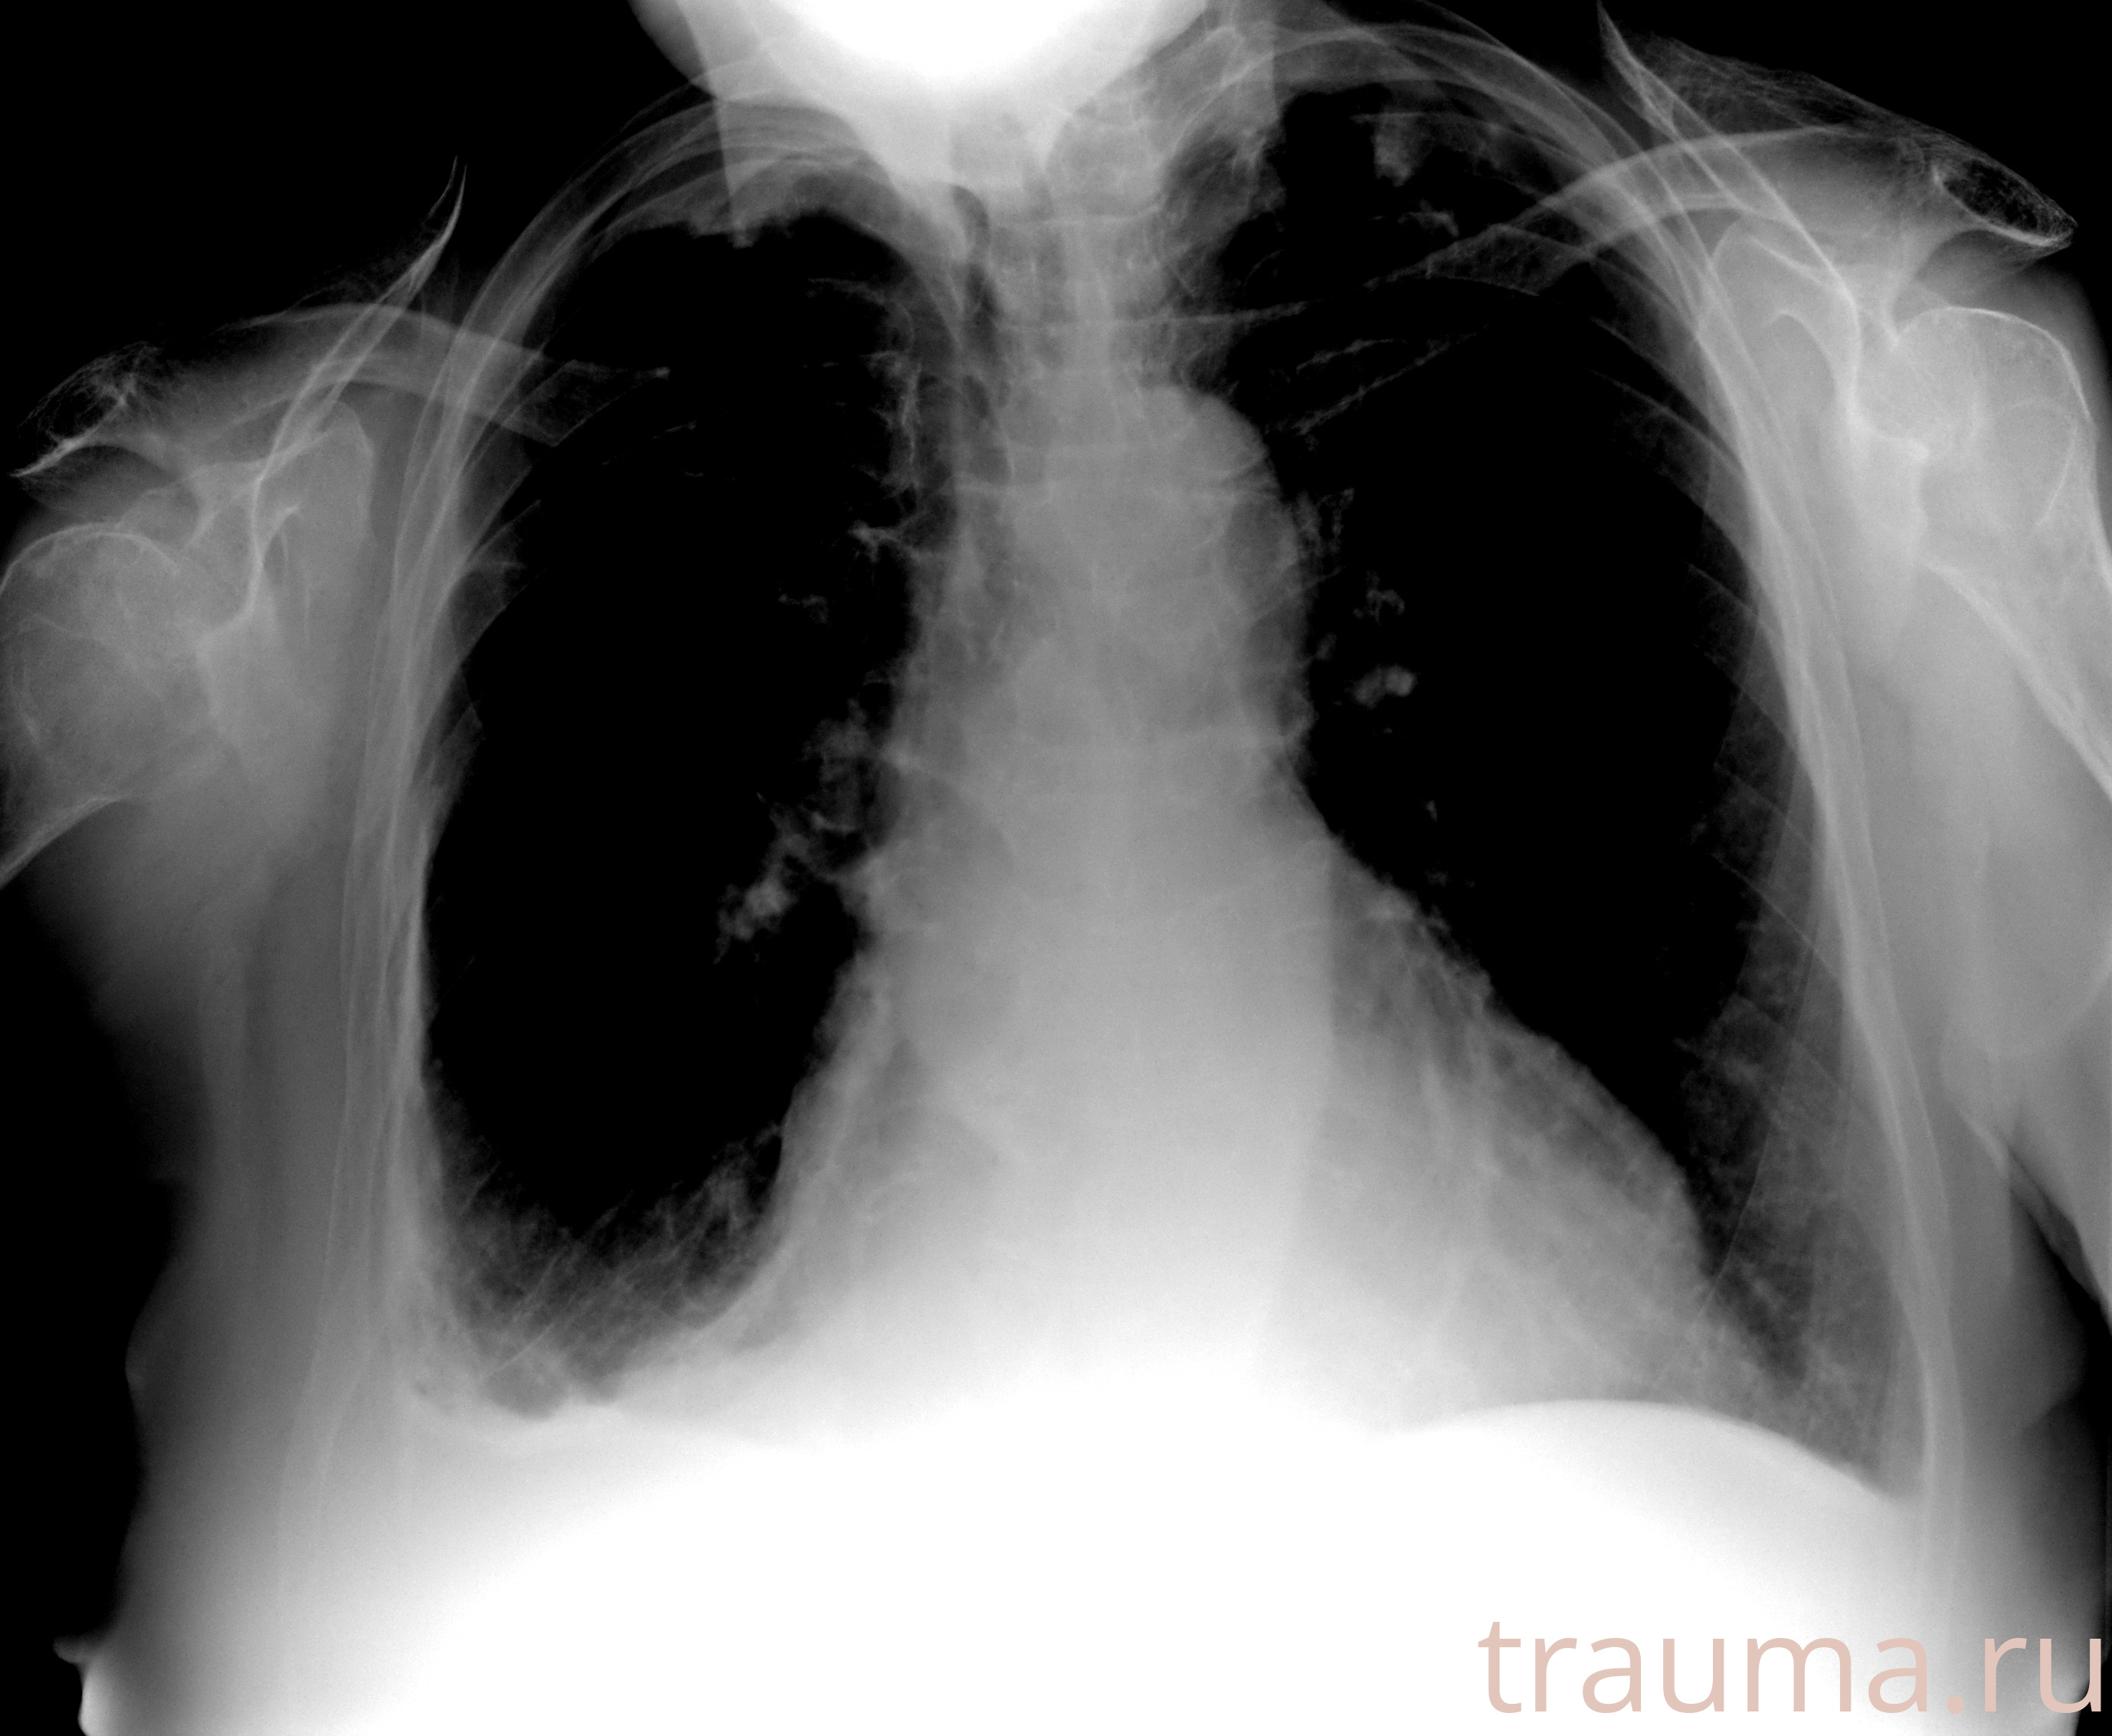

Рентгенограммы

Рентген на дому: по вашему адресу приезжает врач-рентгенолог, травматолог-ортопед с мобильным рентгеновским аппаратом, проводит диагностику травмы или заболевания, делает необходимые рентгенограммы, дает рекомендации по дальнейшему лечению. Получить качественные снимки в домашних условиях возможно благодаря уникальной методике, разработанной МосРентген Центром для института  Склифосовского